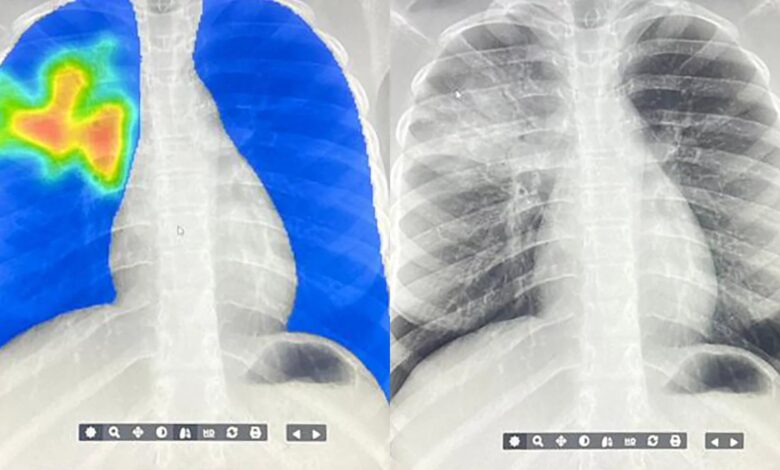

Many low- and middle-income countries are using AI to screen for tuberculosis. This AI model produces what looks like a heat map with spots highlighted in yellow-red that indicate the algorithm detects signs of TB. Image Credit: ARCAD Santé PLUS

AI-powered X-ray screening is transforming the fight against tuberculosis, enabling faster diagnosis in more than 80 low- and middle-income countries where radiologists are scarce.